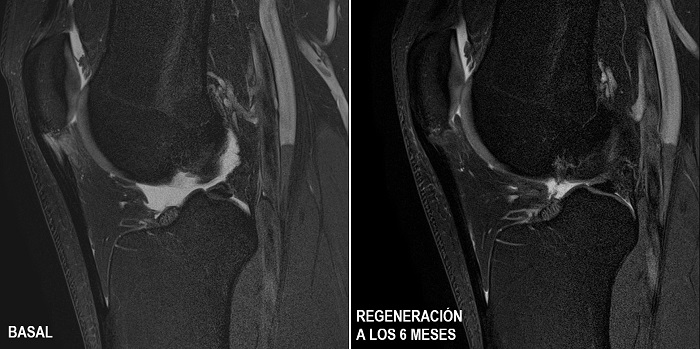

Ambos grupos siguieron tratamiento ambulatorio, sin ingreso hospitalario, y a los seis meses el grupo tratado con células madre mesenquimales cultivadas mostró por primera vez la restauración de la estructura del tendón hasta recuperar un 40 por ciento de la lesión en el 100 por ciento de los pacientes, mientras que el grupo tratado con PRP no mostró ni evolución ni regeneración, incluso superado el periodo de seis meses.